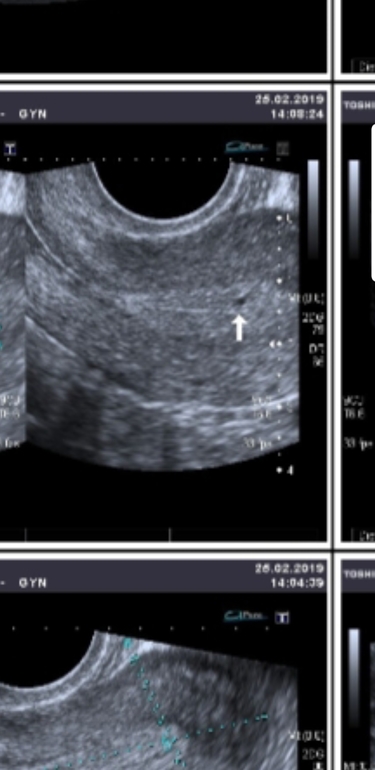

Уже в длинном протоколе ЭКО. Со 2-го сентября должна начаться стимуляция. Сперму мужа заранее заморозили ,т.к. он работает за границей. У нас МФ+ЖФ. Процедура уже полностью оплачена. Сейчас я после дифферелина 3.75. Вчера приняли с мужем решение о разрыве. Точнее , он начал свои "игрища" хочу семейную жизнь/не хочу. Это он любит такой детский сад ,чтобы я начала уговоривать и говорить как он мне нужен. Но вчера меня это окончательно достало. Такие нервотрепки и на такую тему ,когда я уже в протоколе и так на нервах ,конечно : это уже слишком. И игру его на этот раз не поддержала и сразу сказала ок , расходимся. В клинике даже врач восхищалась его желанием иметь ребенка, когда он за несколько часов организовывал срочный многочасовой перелет для ИИ , которая у нас оказалась неожиданно и в планах не была, но придя на очередную консультацию, оказалось,что очень подходящие дни и решили все же попробовать. Теперь в полной растерянности...прододжать протокол без его ведома его спермой... не прлдолжать и просто прервать.. по моему диагнозу у меня снижение овариального резерва АМГ 0.9, 4 антральных фолликула по УЗИ в прошлом месяцем. По УЗИ в протоколе на 2 дц после диферелина пока только один . Растеряна... забыть о нем, обо всем...пытаться строить новую жизнь? Продолжить протокол, а там как Бог даст ?..